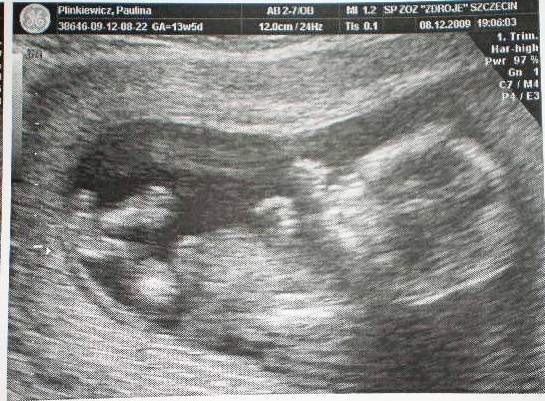

Wklejam moją kruszynkę z wczorajszego USG - ma 4 cm, serduszko bije, to 11 tc. tak się cieszę, jeszcze niedawno myslałam, że to naprawdę niemożliwe.